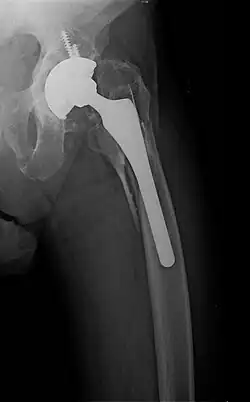

Periprosthetic fracture of left femur

• Periprosthetic fracture – a fracture at the point of mechanical weakness at the end of an implant.